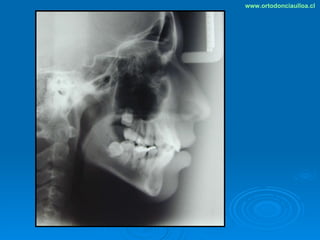

Este documento presenta dos casos clínicos de pacientes que recibieron tratamiento de ortodoncia. El primer caso fue de una paciente femenina de 14 años con apiñamiento dental y mordida cruzada que fue tratada mediante extracción de premolares y alineamiento dental. El segundo caso fue de un paciente masculino de 14 años con clase II esqueletal y desarmonía dentomaxilar que fue tratado con extracción de premolares y corrección de mordida. Ambos casos mostraron mejoría después de 3 años de tratamiento.